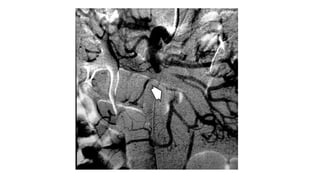

DIAGNOSTICO

• ARTERIOGRAFIA

• No solo confirma el Dx, sino que permite establecer su etiología

• Permite distinguir formas oclusivas de las no oclusivas

• Permite infusión de drogas vasodilatadoras como papaverina y

agentes troboliticos

DIAGNOSTICO • ARTERIOGRAFIA • Nosolo confirma el Dx, sino que permite establecer su etiología • Permite distinguir formas oclusivas de las no oclusivas • Permite infusión de drogas vasodilatadoras como papaverina y agentes troboliticos Moya Calvo M., Acosta Gacho G., et. Al.,Patologia del mesenterio, isquemia intestinal, Medicine, 2008;10(4), pp 231-241